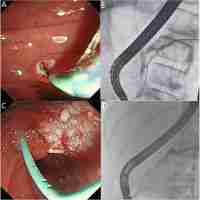

| Abstract | Background: Hepato-pancreato-biliary (HPB) disease has different causes and types between children and adults, which have been diagnosed increasingly in the pediatric group. Endoscopic retrograde cholangiopancreatography (ERCP) has been gradually considered as a therapeutic method in adults, while in pediatric patients, there are not many reports of its usage. This systematic review and meta-analysis aims to assess the use condition of therapeutic ERCP in the management of pediatric HPB diseases. Methods: This systematic literature search was conducted in the PubMed、Embase、Web of Science and the Cochrane library databases to identify all relevant articles published from inception to February 2022 that evaluated therapeutic ERCP in pediatric patients with Hepato-Pancreato-Biliary diseases. The researchers included studies that patients were less than 18 years old and underwent therapeutic ERCP procedures. A random-effects model was used to analyze the usage rate of therapeutic ERCP-procedures, procedural success rates, adverse events rates, and the rate of different therapeutic procedures. Subgroup analysis, sensitivity analysis, and meta-regression were conducted to analyze the source of heterogeneity. Results: A total of 33 articles were included. After homogenization, the overall usage of therapeutic interventions accounts for 77% (95%CI74%-81%) in all ERCP procedures. After excluding outlier studies, the estimation of therapeutic procedure success rate is 74% (95% CI 69 %-79%), adverse events rate is 8% ( 95% CI 6 %-10%). In our study, stent placement is the most common procedure which makes up 75% (95%CI 65%-86%) of all therapeutic procedures. In addition, the usage proportion of sphincterotomy (ST), stone extraction/removal, bougienage/Balloon dilation is respectively 46% (95% CI 39 %-53%), 34% (95% CI 31%-38%), and 26% (95% CI 22%-29%). Conclusions: ERCP procedure is gradually considered as a therapeutic technique in pediatric patients, the proportion of therapeutic ERCP is 77% of total usage, which is increasing by the year. Meanwhile, its success rate is relatively high. It reflects that this operation modality is promising in the treatment of Hepato-pancreato-biliary disorders and is gradually expanded as more branch technologies are being used. A variety of operations can be achieved through ERCP procedures, and more functions should be developed in the future. |